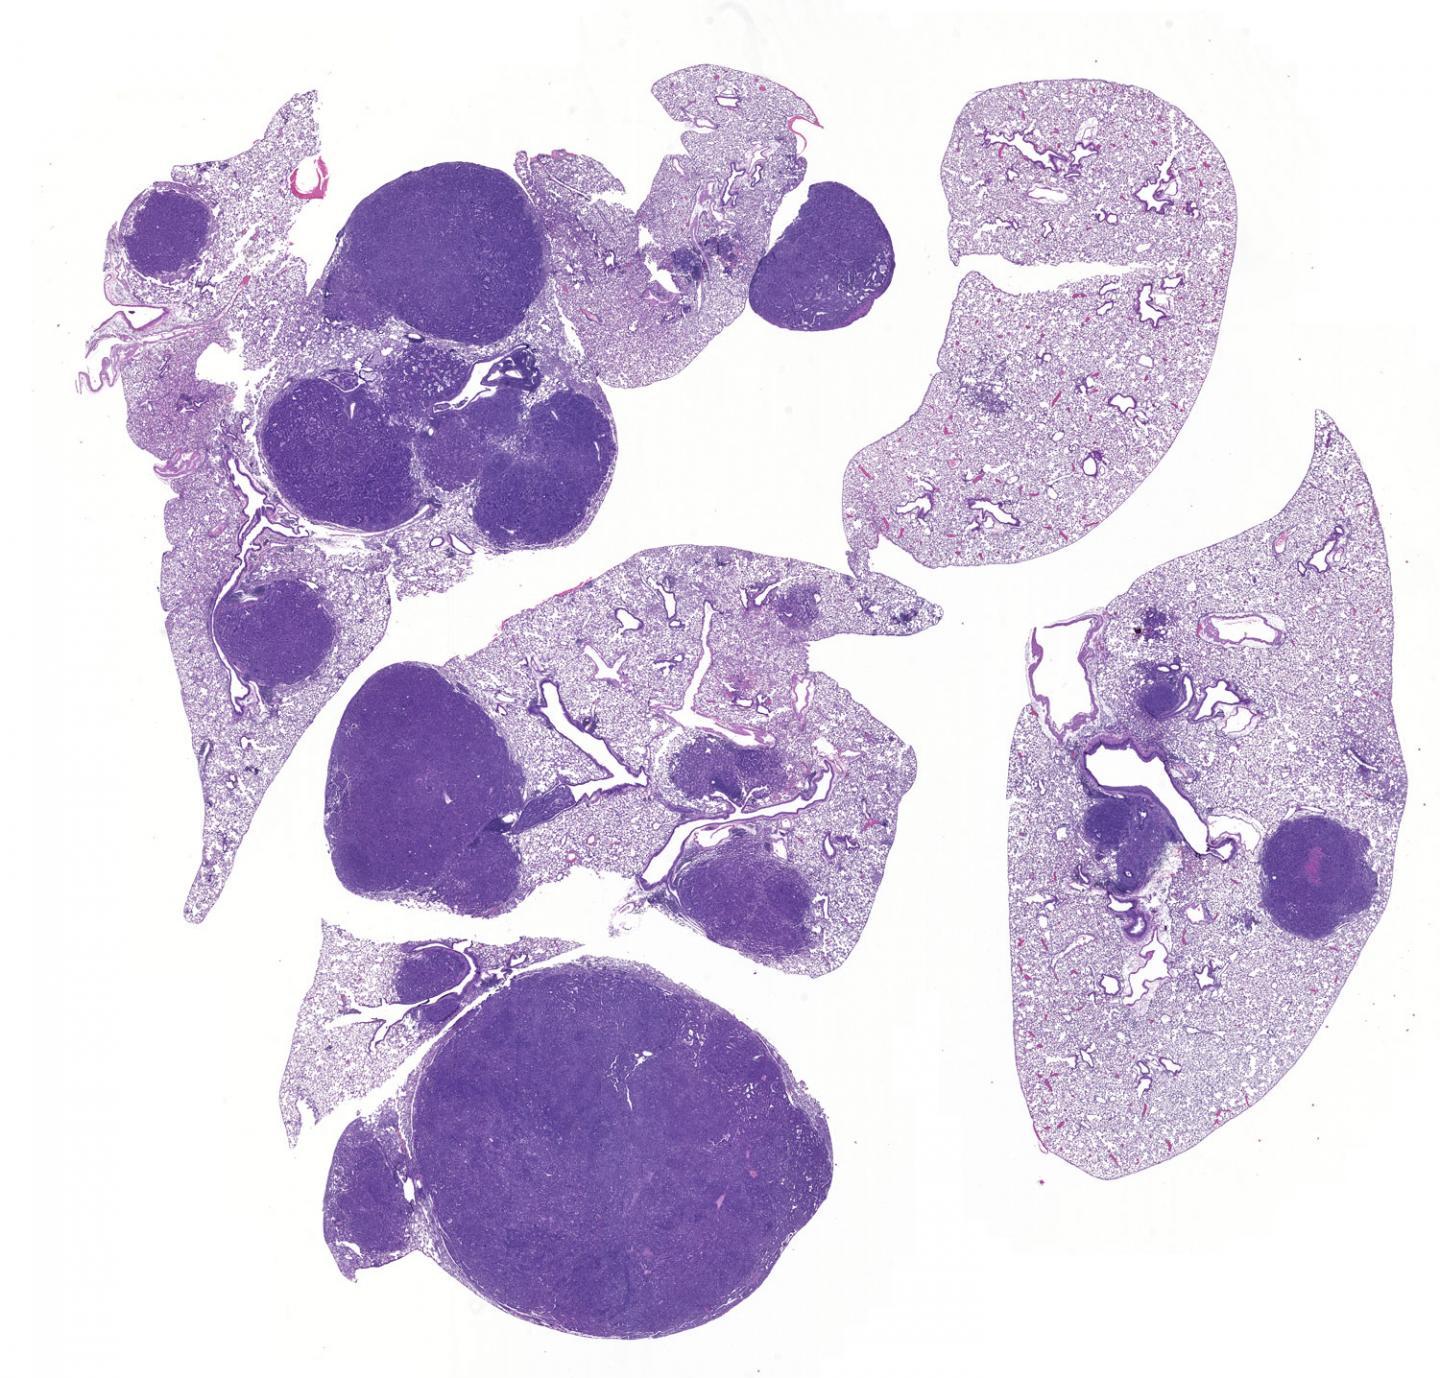

LA JOLLA--(July 26, 2019) The vast majority of deadly lung cancer cases (85 percent) are termed non-small-cell lung carcinomas (NSCLCs), which often contain a mutated gene called LKB1. Salk Institute researchers have now discovered precisely why inactive LKB1 results in cancer development. The surprising results, published in the online version of Cancer Discovery on July 26, 2019, highlight how LBK1 communicates with two enzymes that suppress inflammation in addition to cell growth, to block tumor growth. The findings could lead to new therapies for NSCLC.

To figure it out, the team used CRISPR technology combined with genetic analysis to inactivate each suspected kinase one at a time and then in combinations. They observed how the inactivations affected tumor growth and development in both cell cultures of NSCLC cells and in a genetic NSCLC mouse model. The experiments pointed the researchers to two kinases: one called SIK1 had the strongest effect in stopping tumors from forming. When SIK1 was inactivated, tumor growth increased; and when a related kinase, SIK3, was also inactivated, the tumor grew even more aggressively.